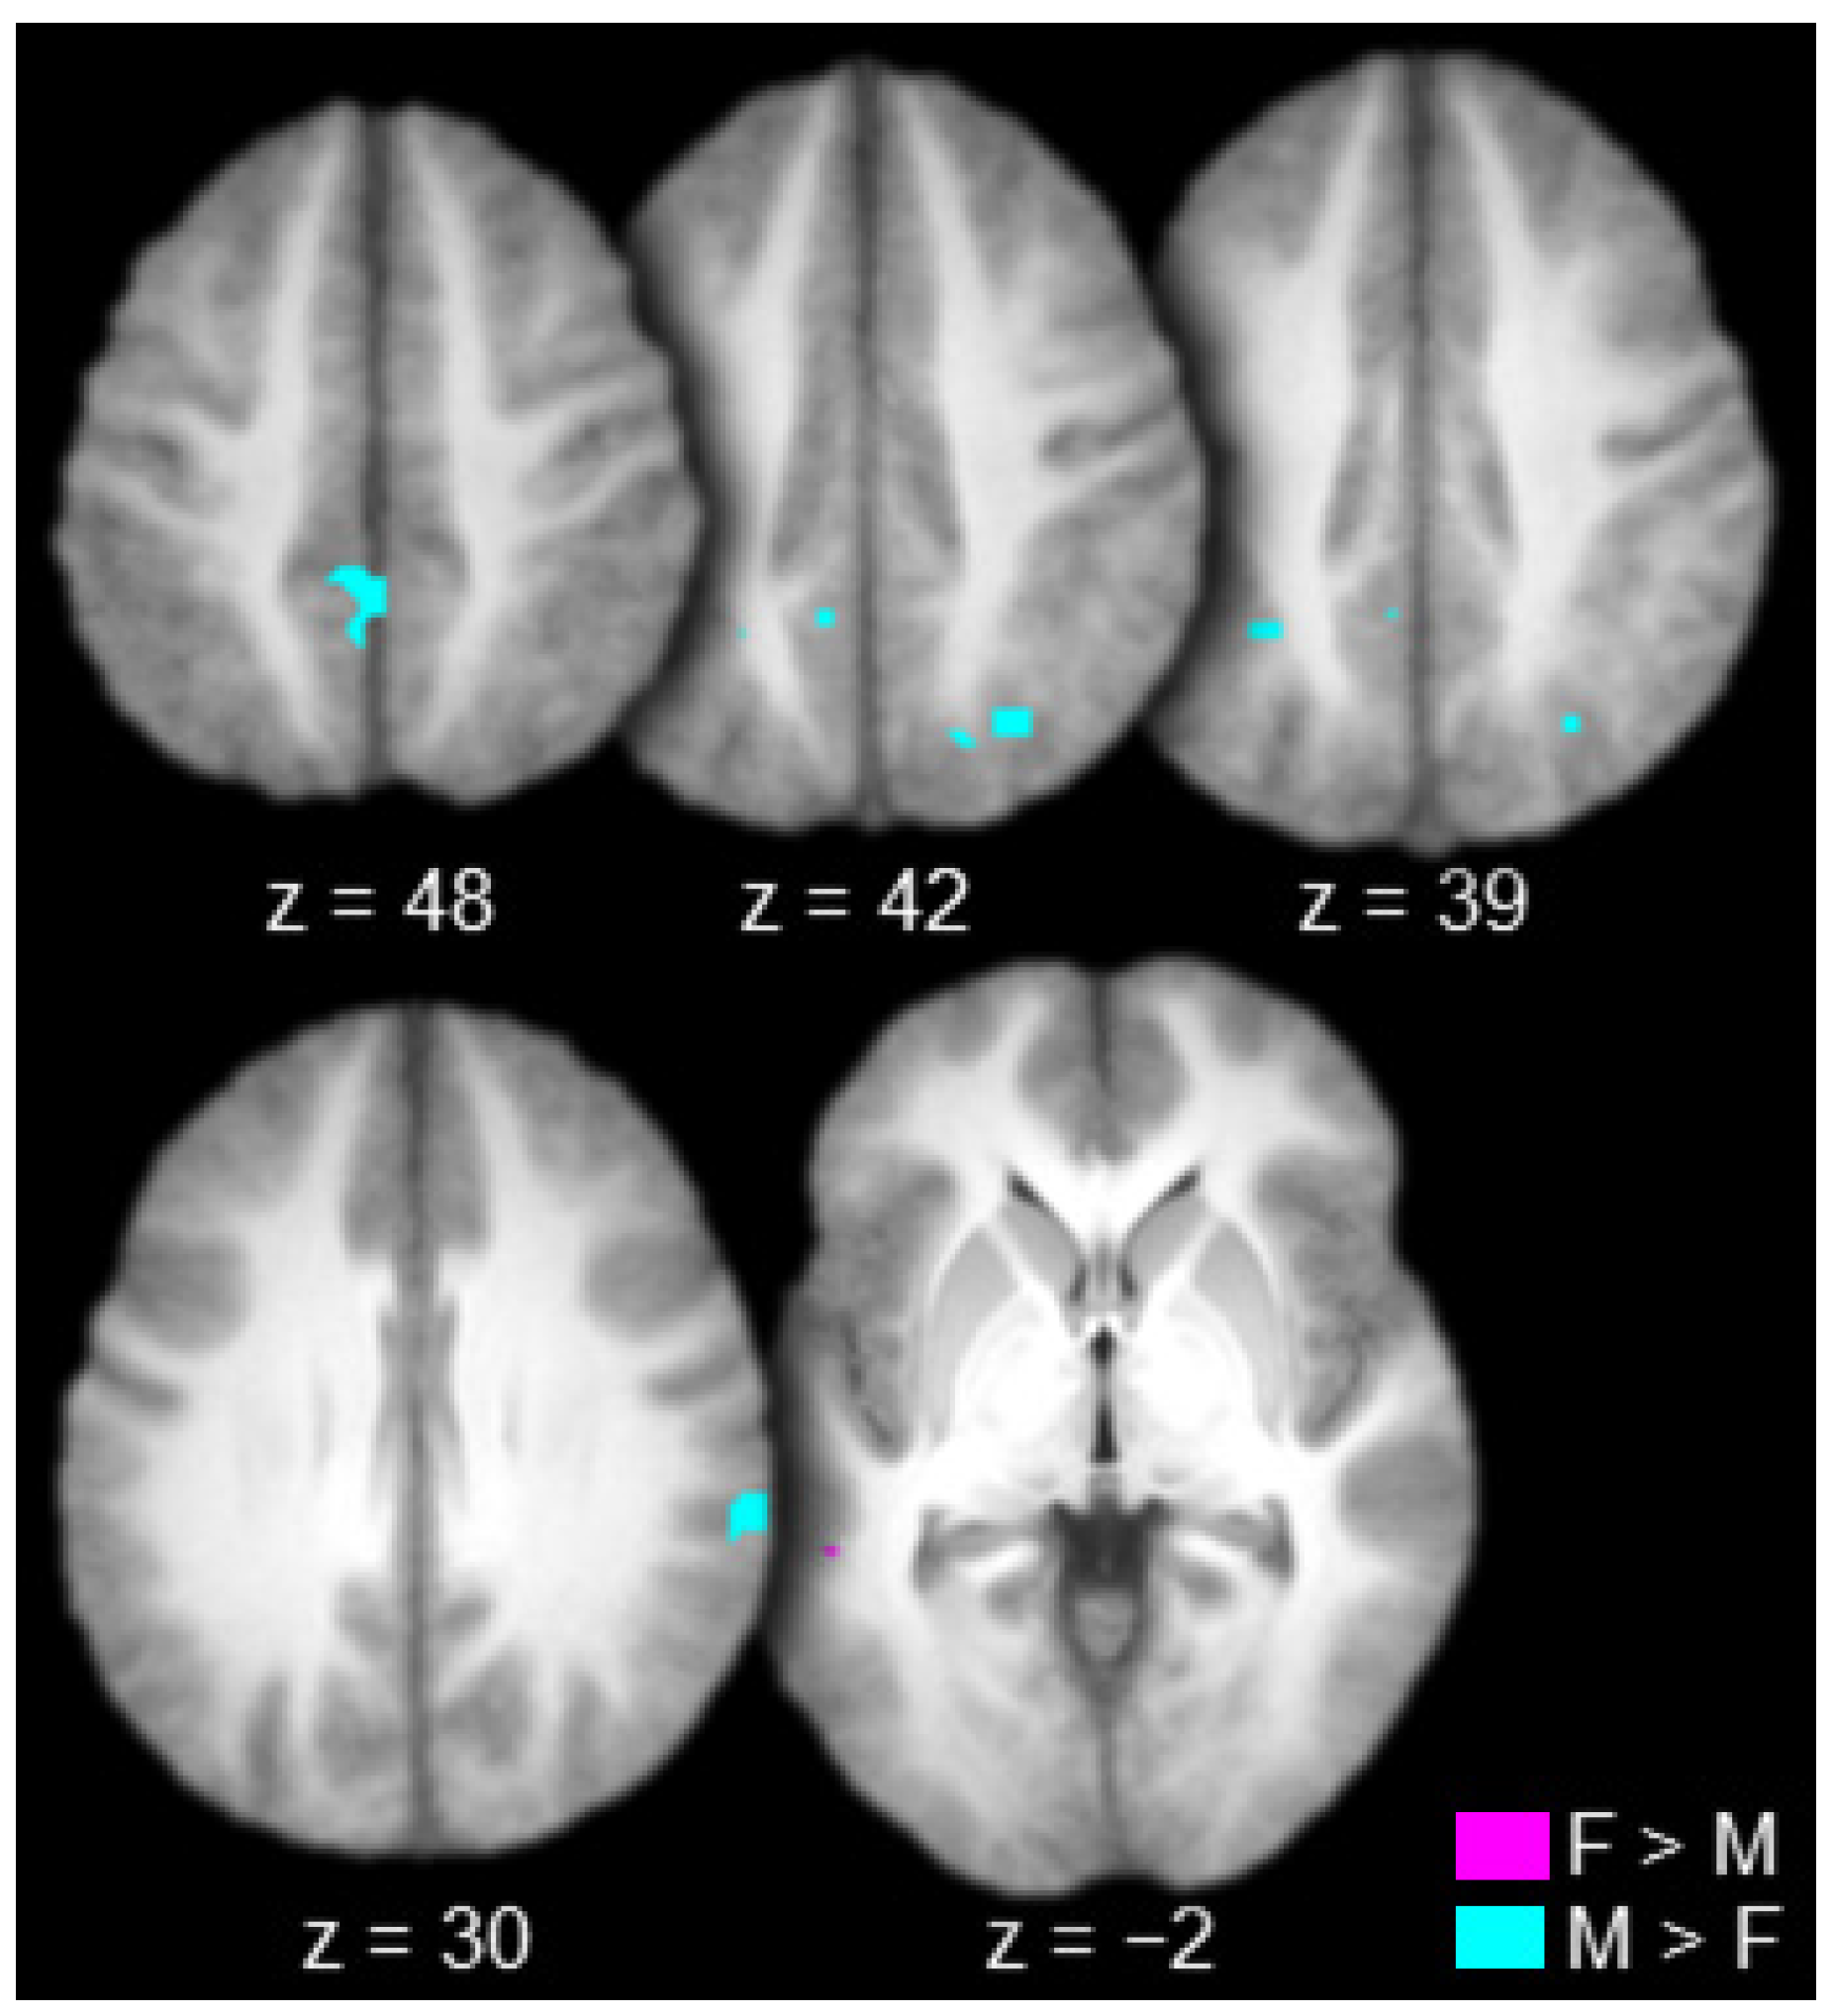

| Female (Hits > Misses) > Male (Hits > Misses) | |||||

| Positive activations | |||||

| L. Superior Temporal Sulcus | 22 | −48 | −41 | −2 | 31 |

| Male (Hits > Misses) > Female (Hits > Misses) Negative activations | |||||

| R. Supramarginal Gyrus | 40 | 61 | −31 | 29 | 40 |

| L. Intraparietal Sulcus | 7/40 | −28 | −48 | 40 | 24 |

| R. Intraparietal Sulcus | 19/39 | 28 | −67 | 42 | 37 |

| Bilateral Precuneus/Post. Cingulate Gyrus | 7/31 | 0 | −42 | 48 | 55 |